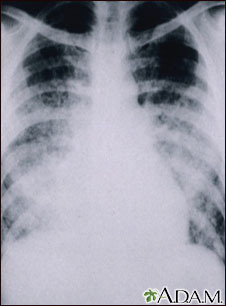

This chest x-ray shows cloudiness throughout the lungs, caused by acute pneumonia following chickenpox. Pneumonia, as a complication of chickenpox, rarely occurs in children, but occurs in about one-fifth of adults.